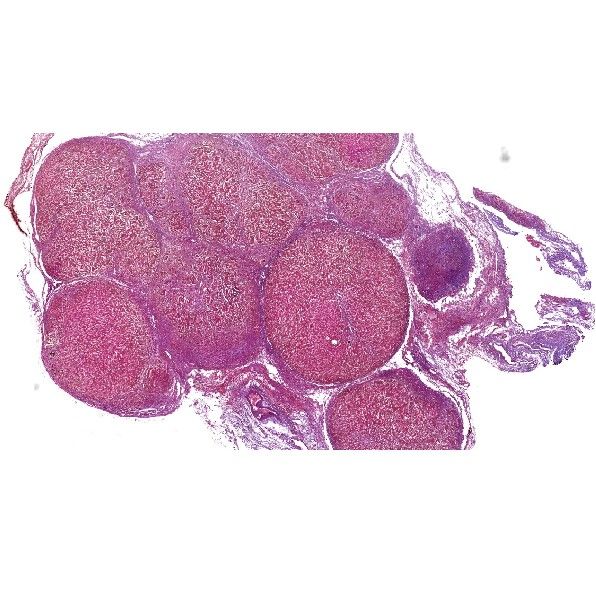

小鼠肝Masson染色.

Masson染色